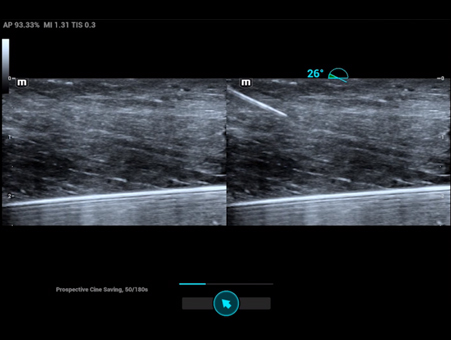

Reimagined safety and adaptability

MindrayŌĆÖs Anesthesia Ultrasound solutions address your biggest perioperative challenges such as treatment efficacy and patient safety, to improve patient outcomes in the operating room. We recognize the human side of healthcare and your role in providing best-in-class patient care, which is why we designed products suited to your clinical needs in this environment.